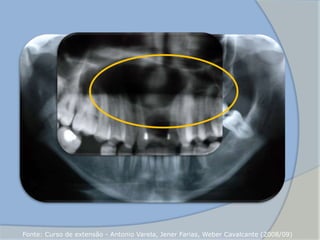

 Forma-se no interior do alvéolo

 Radio transparência de forma circular a oval

2. Cisto Periapical

Residual

(CASTRO et al, 2008)